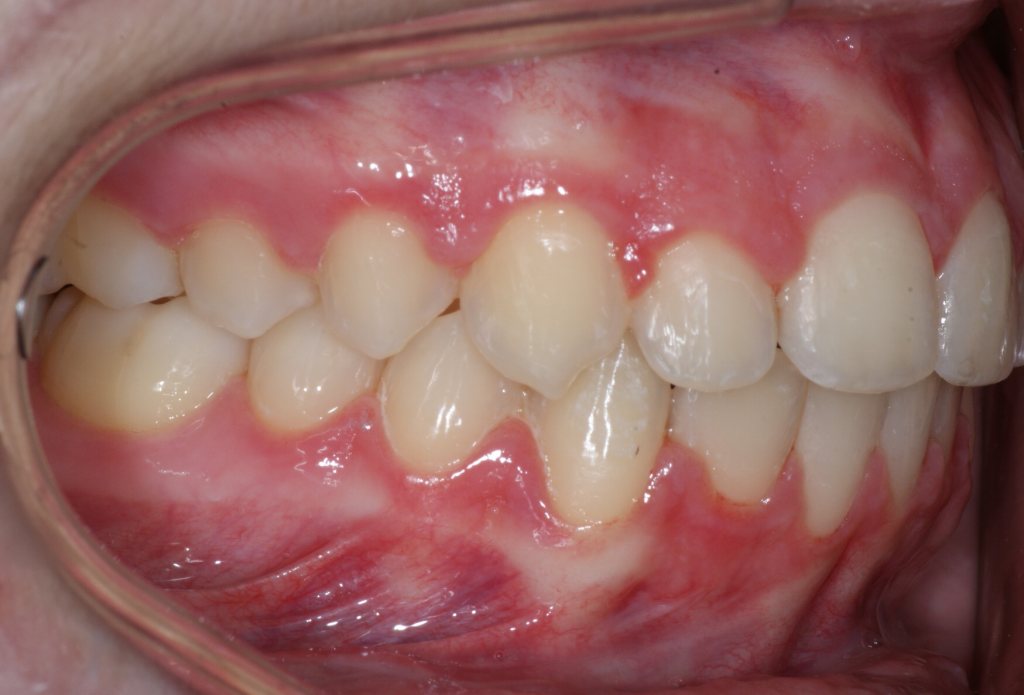

Dans la majorité des cas, un traitement complet est requis afin de corriger la malocclusion et procéder à la traction des canines incluses. Le temps de traitement varie en fonction de l’âge du patient, de la position des canines incluses et de la sévérité de la malocclusion. Ici, nous avons dû procéder à la traction de la canine incluse inférieure droite (#43). La durée du traitement fut de 19 mois, ce qui est exceptionnel puisque habituellement, on parle plus de 24 à 30 mois de traitement pour faire la traction d’une canine.